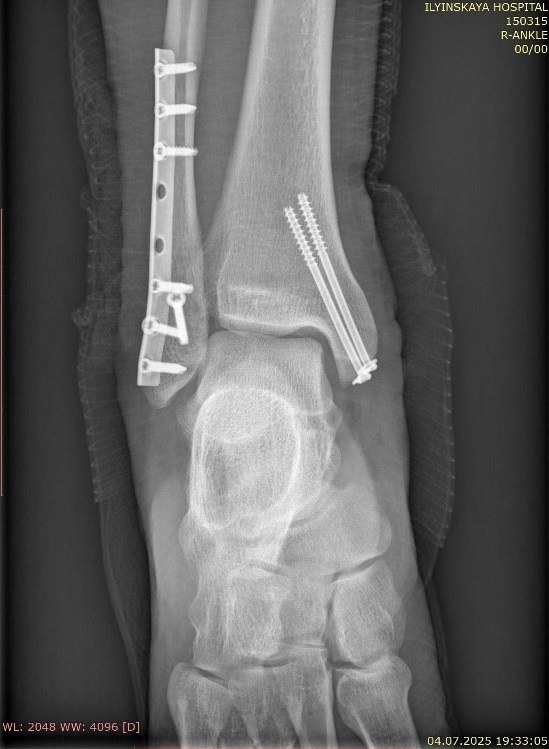

ΠŸΠ°Ρ†ΠΈΠ΅Π½Ρ‚ ΠΏΠΎΡΠΊΠΎΠ»ΡŒΠ·Π½ΡƒΠ»ΡΡ Π½Π° ΠΌΠΎΠΊΡ€ΠΎΠΉ послС доТдя повСрхности ΠΈ ударился ΠΏΡ€Π°Π²ΠΎΠΉ стопой. Π’ Ρ€Π΅Π·ΡƒΠ»ΡŒΡ‚Π°Ρ‚Π΅ ΠΎΠ½ ΠΏΠΎΠ»ΡƒΡ‡ΠΈΠ» ΡΠ»Π΅Π΄ΡƒΡŽΡ‰ΠΈΠ΅ поврСТдСния:

πŸ”ΉΠŸΠ΅Ρ€Π΅Π»ΠΎΠΌ Ρ‚Ρ€Ρ‘Ρ… костных структур, Ρ„ΠΎΡ€ΠΌΠΈΡ€ΡƒΡŽΡ‰ΠΈΡ… сустав: ΠΎΠ±Π΅ΠΈΡ… Π»ΠΎΠ΄Ρ‹ΠΆΠ΅ΠΊ ΠΈ Π·Π°Π΄Π½Π΅Π³ΠΎ края Π±ΠΎΠ»ΡŒΡˆΠ΅Π±Π΅Ρ€Ρ†ΠΎΠ²ΠΎΠΉ кости.

πŸ”ΉΠ’Ρ‹Π²ΠΈΡ… стопы ΠΊΠ½Π°Ρ€ΡƒΠΆΠΈ.

πŸ”ΉΠŸΠΎΠ²Ρ€Π΅ΠΆΠ΄Π΅Π½ΠΈΠ΅ (ΠΊΠ°ΠΊ ΠΌΠΈΠ½ΠΈΠΌΡƒΠΌ частичный Ρ€Π°Π·Ρ€Ρ‹Π²) Π΄ΠΈΡΡ‚Π°Π»ΡŒΠ½ΠΎΠ³ΠΎ ΠΌΠ΅ΠΆΠ±Π΅Ρ€Ρ†ΠΎΠ²ΠΎΠ³ΠΎ синдСсмоза – Π³Π»Π°Π²Π½ΠΎΠΉ связки, ΡΡ‚Π°Π±ΠΈΠ»ΠΈΠ·ΠΈΡ€ΡƒΡŽΡ‰Π΅ΠΉ голСностопный сустав.

ΠŸΠ΅Ρ€Π²ΠΈΡ‡Π½Π°Ρ ΠΏΠΎΠΌΠΎΡ‰ΡŒ: пСрвостСпСнной Π·Π°Π΄Π°Ρ‡Π΅ΠΉ Π±Ρ‹Π»ΠΎ устранСниС Π³Ρ€ΡƒΠ±ΠΎΠ³ΠΎ смСщСния ΠΎΡ‚Π»ΠΎΠΌΠΊΠΎΠ² ΠΈ Π²Ρ‹Π²ΠΈΡ…Π° для дСкомпрСссии ΠΌΠ°Π³ΠΈΡΡ‚Ρ€Π°Π»ΡŒΠ½Ρ‹Ρ… сосудов ΠΈ Π½Π΅Ρ€Π²ΠΎΠ², ΠΈΡΠΊΠ»ΡŽΡ‡Π΅Π½ΠΈΡ риска ΠΏΠΎΡ‚Π΅Ρ€ΠΈ конСчности. По мСсту Ρ‚Ρ€Π°Π²ΠΌΡ‹ Π²Ρ‹Π²ΠΈΡ… Π±Ρ‹Π» устранён ΠΈ ΠΏΡ€ΠΎΠΈΠ·Π²Π΅Π΄Π΅Π½Π° иммобилизация.

ΠŸΠΎΡΡ‚ΡƒΠΏΠ»Π΅Π½ΠΈΠ΅ ΠΊ Π½Π°ΠΌ: Π΄Π°Π½Π½Ρ‹ΠΉ Ρ‚ΠΈΠΏ ΠΏΠ΅Ρ€Π΅Π»ΠΎΠΌΠ° ΠΈΡΠΊΠ»ΡŽΡ‡Π°Π΅Ρ‚ Π²ΠΎΠ·ΠΌΠΎΠΆΠ½ΠΎΡΡ‚ΡŒ ΠΎΠΊΠΎΠ½Ρ‡Π°Ρ‚Π΅Π»ΡŒΠ½ΠΎΠΉ фиксации Π² экстрСнном порядкС («с колёс») ΠΈΠ·-Π·Π° ΠΎΡ‡Π΅Π½ΡŒ высокого риска Ρ€Π°Π½Π΅Π²Ρ‹Ρ… ослоТнСний. ΠŸΠ΅Ρ€Π²Π°Ρ нСдСля Π±Ρ‹Π»Π° посвящСна Π±ΠΎΡ€ΡŒΠ±Π΅ с ΠΎΡ‚Ρ‘ΠΊΠΎΠΌ мягких Ρ‚ΠΊΠ°Π½Π΅ΠΉ.

ΠžΠΊΠΎΠ½Ρ‡Π°Ρ‚Π΅Π»ΡŒΠ½ΠΎΠ΅ Π»Π΅Ρ‡Π΅Π½ΠΈΠ΅: Ρ€Π΅Π°Π»ΠΈΠ·ΠΎΠ²Π°Π½Π° ΠΎΠΏΡ‚ΠΈΠΌΠ°Π»ΡŒΠ½Π°Ρ хирургичСская Ρ‚Π°ΠΊΡ‚ΠΈΠΊΠ° - фиксация ΠΎΠ±Π΅ΠΈΡ… Π»ΠΎΠ΄Ρ‹ΠΆΠ΅ΠΊ, ΠΎΠ±Π΅ΡΠΏΠ΅Ρ‡ΠΈΠ²Π°ΡŽΡ‰Π°Ρ Π΄ΠΎΡΡ‚Π°Ρ‚ΠΎΡ‡Π½ΡƒΡŽ ΡΡ‚Π°Π±ΠΈΠ»ΡŒΠ½ΠΎΡΡ‚ΡŒ для Ρ€Π°Π½Π½ΠΈΡ… Π°ΠΊΡ‚ΠΈΠ²Π½Ρ‹Ρ… Π΄Π²ΠΈΠΆΠ΅Π½ΠΈΠΉ Π² голСностопном суставС.

РСабилитация: с ΠΏΠ΅Ρ€Π²ΠΎΠ³ΠΎ послСопСрационного дня ΠΏΠ°Ρ†ΠΈΠ΅Π½Ρ‚ приступил ΠΊ занятиям Π»Π΅Ρ‡Π΅Π±Π½ΠΎΠΉ Ρ„ΠΈΠ·ΠΊΡƒΠ»ΡŒΡ‚ΡƒΡ€ΠΎΠΉ (Π›Π€Πš) ΠΈ пСрСдвигался с использованиСм приспособлСния, ΠΏΠΎΠ·Π²ΠΎΠ»ΡΡŽΡ‰Π΅Π³ΠΎ Π½Π°ΡΡ‚ΡƒΠΏΠ°Ρ‚ΡŒ Π½Π° ΠΏΠΎΠ²Ρ€Π΅ΠΆΠ΄Ρ‘Π½Π½ΡƒΡŽ Π½ΠΎΠ³Ρƒ Ρ‡Π΅Ρ€Π΅Π· ΠΊΠΎΠ»Π΅Π½Π½Ρ‹ΠΉ сустав ΠΈ ΠΏΡ€ΠΈ этом Π½Π΅ Π½Π°Π³Ρ€ΡƒΠΆΠ°Ρ‚ΡŒ ΠΎΠ±Π»Π°ΡΡ‚ΡŒ ΠΏΠ΅Ρ€Π΅Π»ΠΎΠΌΠ°.